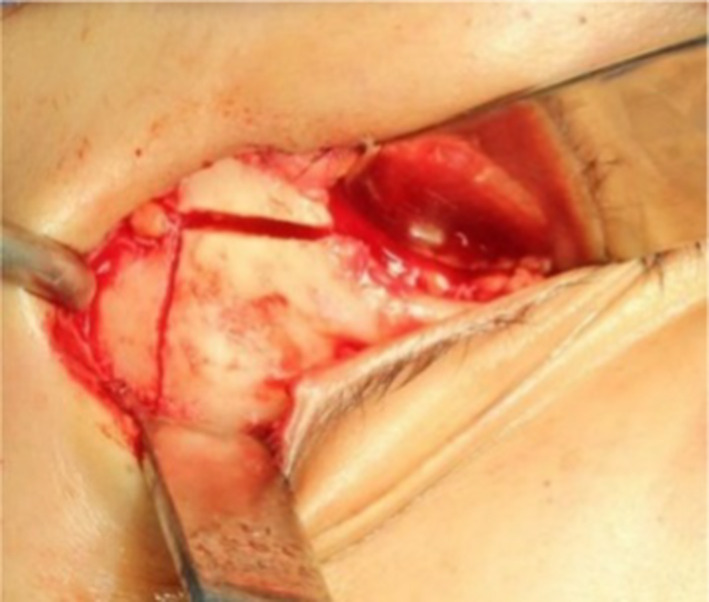

Fig. 8.

Posterior view of the pterygomaxillary guide with a security hook to stop the oscillating saw from entering the pterygomaxillary fossa and the inferior orbital content. The pink triangle corresponds to the danger zone in which the maxillary artery could be injured

We will explain the above in detail, the osteotomy of the pterygomaxillary fossa. The disjunction of the pterygoid processes is exactly the same as in the Le Fort I Type Osteotomy; however, an ascending oblique linear osteotomy with a length of 4 to 4.5 cm in its entirety is required. The osteotomy is performed in two sections with an oscillating saw (7 mm saw for women and 12 mm for men). The first section goes from the pterygoid junction until it reaches below the posterior buttress, sinking the saw blade completely, to have a better view it is recommended to remove the fat bag of bichat. The second section will be performed following the direction marked by a surgical guide (green) designed on a stereolithographic model. The osteotomy is performed at this level with the 7 mm oscillating blade regardless of whether it is a female or male patient, this step is performed by exclusively sinking half of the saw into the bone until reaching the orbital floor, specifically the osteotomy is finished at 5 mm ahead of the inferior orbital fissure. All of this osteotomy takes place within the pterygomaxillary fossa.